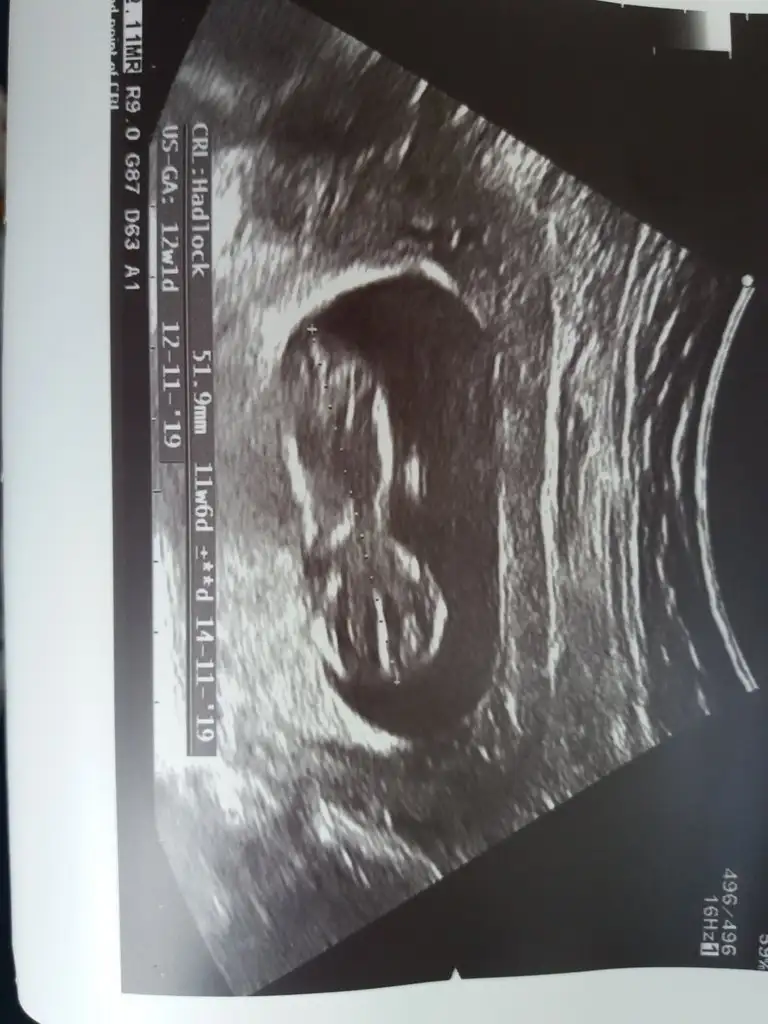

Canim 12 hafta 2 gunluk. Seninki?Normalde adet tarihime gore 14 hafta 2 gunluk olmasi lazimdi.iyi canım, peki kaç haftalıktın tam . benimki de geç döllenmeydi

canım benimki de bugün 13 haftalık tam . benimki de adete göre 14 hafta olmalıydıCanim 12 hafta 2 gunluk. Seninki?Normalde adet tarihime gore 14 hafta 2 gunluk olmasi lazimdi.